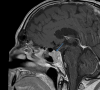

Giant cell arteritis is the most common primary systemic vasculitis among individuals over 50 years of age. It primarily affects large- and medium-size arteries and is not mediated by antibodies. One of the most recognizable and important symptoms of the disease is headache. The presence of headaches, along with other common cranial manifestations such as vision loss, jaw claudication, and scalp tenderness in the temporal arteries, can assist in diagnosing the condition. We present a complex case involving a 76-year-old male with prolonged headaches, a pituitary macroadenoma, and vestibular schwannoma. Initially, his headaches were attributed to his existing intracranial lesions; however, his symptoms continued to evolve. He continued to have headaches of varying intensity over 2 years, and subsequently developed diffuse scalp tenderness, visual disturbances, and tongue claudication. Input from various medical specialties expanded the differential diagnosis and raised the possibility of giant cell arteritis (GCA). Although the temporal artery biopsy did not reveal the classic giant cells typically associated with the condition, it supported the clinical diagnosis of GCA. Appropriate treatment with high-dose corticosteroids and anti-Interleukin 6 therapy resulted in the rapid resolution of his symptoms. This case emphasizes the importance of recognizing different types of headaches, maintaining a broad differential diagnosis, and thoroughly evaluating all clinical symptoms for timely diagnosis and treatment. It also highlights the significance of a multidisciplinary approach to ensure prompt diagnosis and to prevent irreversible complications, such as permanent vision loss.